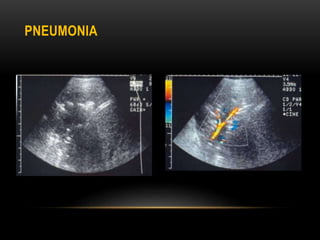

PNEUMONIA

 Consolidation can be visualized on ultrasound

 Appears as hypoechoic area with irregular margins

 Branching echogenic structures are often seen within the

consolidation and represent air bronchograms

 Air bronchogram may be seen as hyperechoic foci moving through

the bronchi(dynamic air bronchogram)within the consolidation

 The branching pattern of vascular flow with in the consolidated

lung segment can be observed by using color Doppler

PNEUMONIA  Consolidation canbe visualized on ultrasound  Appears as hypoechoic area with irregular margins  Branching echogenic structures are often seen within the consolidation and represent air bronchograms  Air bronchogram may be seen as hyperechoic foci moving through the bronchi(dynamic air bronchogram)within the consolidation  The branching pattern of vascular flow with in the consolidated lung segment can be observed by using color Doppler

• #32 USG image showing an area of consolidation with in the right lower lobe .the texture of the consolidated lung appear isoechoic to the liver. multiple echogenic foci are seen within the consolidated lung and correspond to air filled airways On the color doppler scan, a pulmonary artery branch supplying the segment is clearly seen in pneumonia we lose a lines